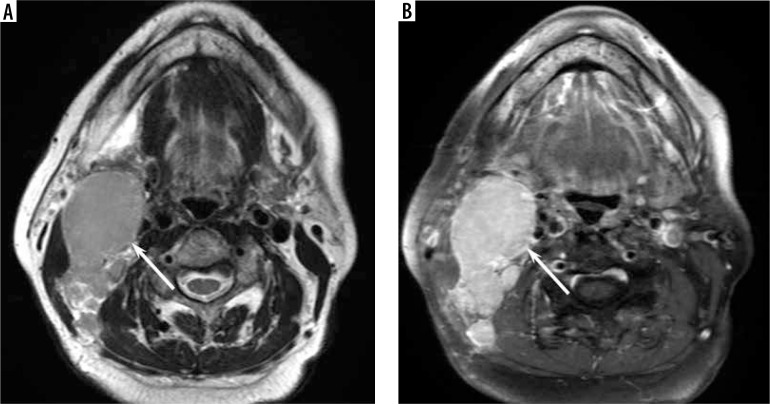

Results: The maximum diameter (22.4 ± 6.9 vs. 33.3 ± 16.0 mm, p < 0.01), minimum diameter (15.8 ± 3.6 vs. 22.3 ± 8.5 mm, p < 0.01), and SUVmax (6.9 ± 2.7 vs. 12.8 ± 8.0, p < 0.01) of the lesion were lower in reactive lymphadenitis than in nodal lymphoma, respectively. T2-hypointense-thickened capsules > 2 mm (46% vs. 14%, p < 0.05) and T2-hypointense areas converging to the periphery (15% vs. 0%, p < 0.05) were more frequently observed in reactive lymphadenitis than in nodal lymphoma, respectively. Hilum of nodes on T2-weighted images (54% vs. 22%, p < 0.05) and diffusion-weighted images (69% vs. 30%, p < 0.05) were more frequently demonstrated in reactive lymphadenitis than in nodal lymphoma, respectively.

Conclusions: Reactive lymphadenitis had a smaller size and lower SUVmax. The presence of T2-hypointense-thickened capsules, T2-hypointense areas converging to the periphery, and hilum of nodes were signs of reactive lymphadenitis.